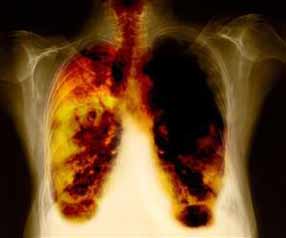

Cuba is constantly working not only on early detection but also on the development of new drugs to treat the disease. According to recent health authority figures, 67% of all clinical research in Cuba today is aimed at the discovery of effective treatments for different types of cancer. Cuban medical and pharmaceutical industry largely aims its research at developing vaccines to prevent cancer and, as a result, lower the people's medication expenses. In 2012, Cuba patented the first therapeutic vaccine in the world against advanced lung cancer, called CIMAVAX-EGF. In January 2013, the island announced the second cancer vaccine, known as Racotumomab (VAXIRA). Clinical tests, carried out in 86 nations, revealed that though these vaccines do reduce the tumors thus improving the quality and expectancy of life of the patients.

Cimavax has proven to be one of the most effective ways to treat lung cancer in late stages (IIIB to IV).

The vaccine works by targeting the protein called epidermal growth factor (EGF). Many cancers will force the body to produce large amounts of EGF which makes the cells grow and divide and unable to control. Cimavax is partially composed of EGF and tells the body to create antibodies which identify and bind to the EGF stopping it from being able to attach to the receptors of the cancer cells. By doing this, Cimavax will cut off the signal that the cancer sends to its cell to grow and divide which in return will slow down the growth of the lung cancer. The Cimavax vaccine does not prevent lung cancer, but it can change patient's condition from life threatening to a chronic and manageable condition.

Cuban researchers designed the vaccine for non-small cells lung cancer (NSCLC), the most common type. But the concept is applicable to other cancers, such as prostate, breast and colon.